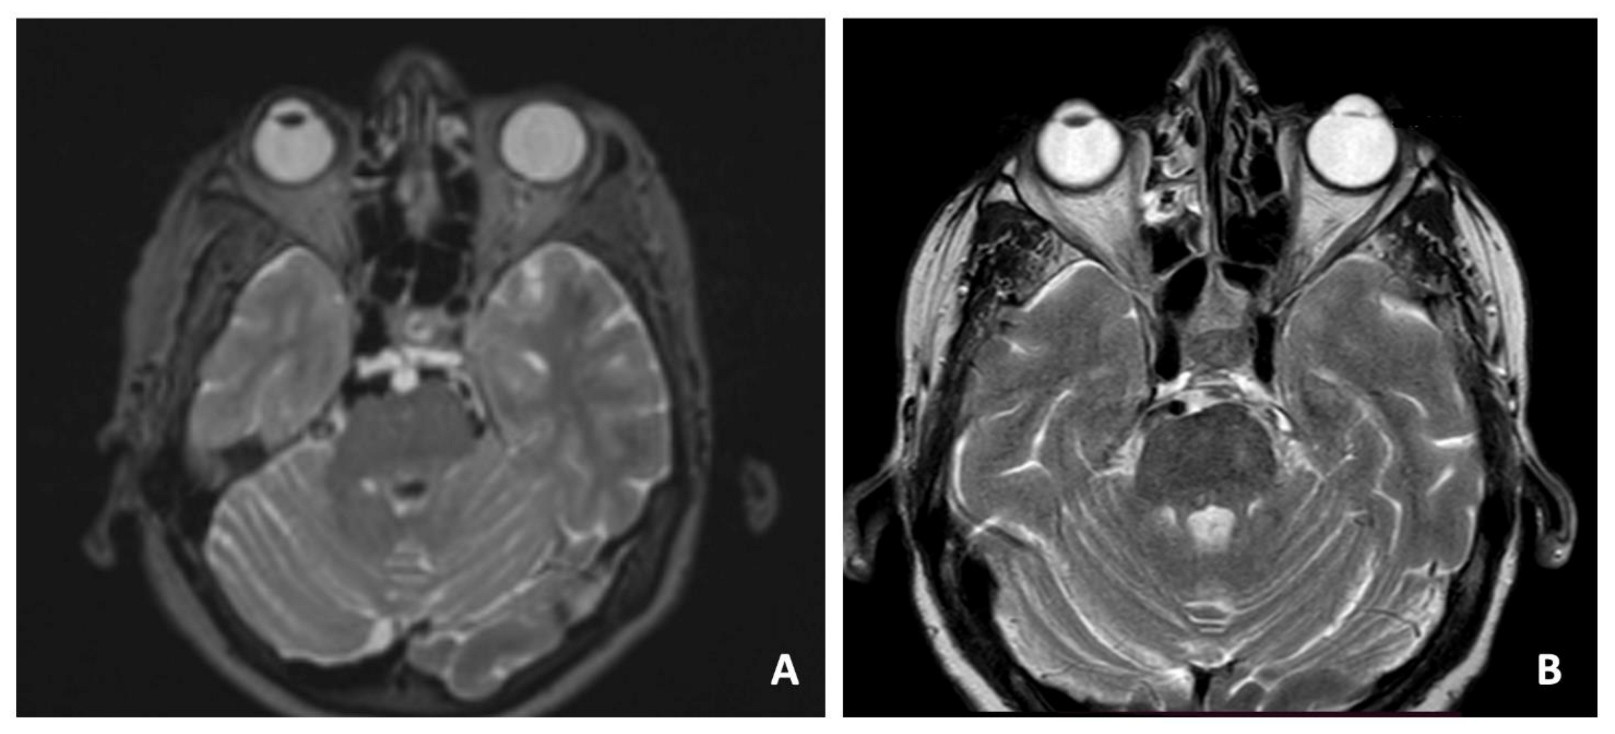

3.1. Case 1—Clival Osteoradionecrosis

3.2. Case 2—Ecchordosis Physaliphora